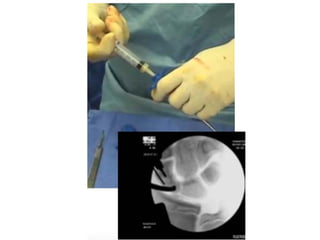

This presentation discusses various topics related to the wrist including static scapholunate ligament dissociation, dorsal ganglion cysts originating from the dorsal capsulolunate septum, treatment of scaphoid pseudarthrosis using a bone graft from the distal radius placed under the extensor tendons, and proximal pole scaphoid pseudarthrosis treated with capitolunate arthrodesis. It also thanks attendees and provides instructions for accessing the presentation online.